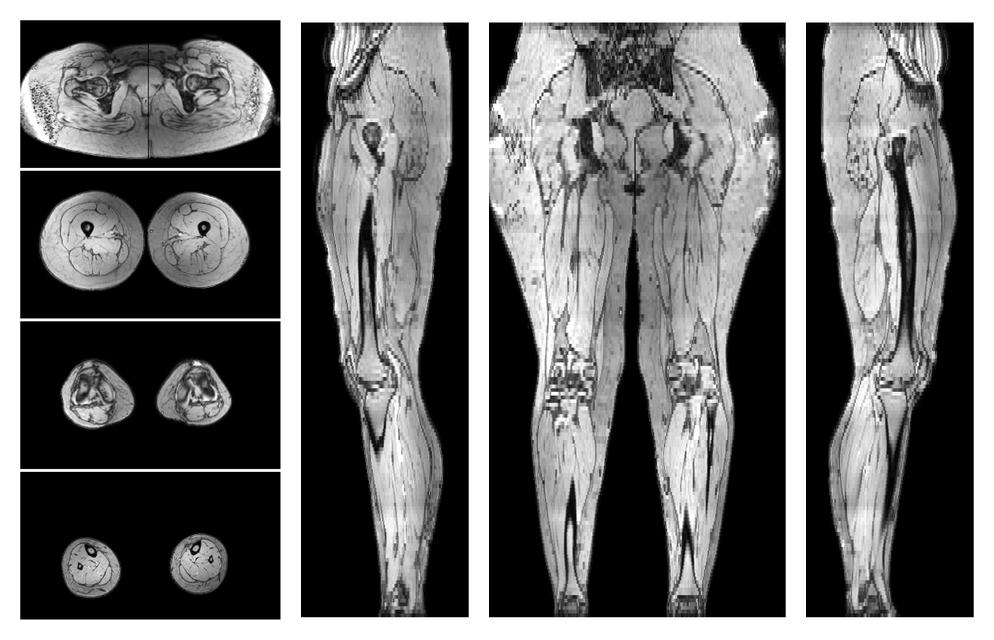

• Water only signal

The water part of the acquired multi-echo spin echo data.

• Water only T2 relaxation time

The water only T2 relaxation time of the lower extremity obtained from multi echo spin echo t2 mapping with EPG based reconstruction.